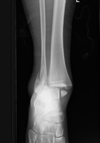

Trauma

Fratura do platô tibial lateral - Schatzker tipo 2 (traço de fratura + depressão do plato lateral).